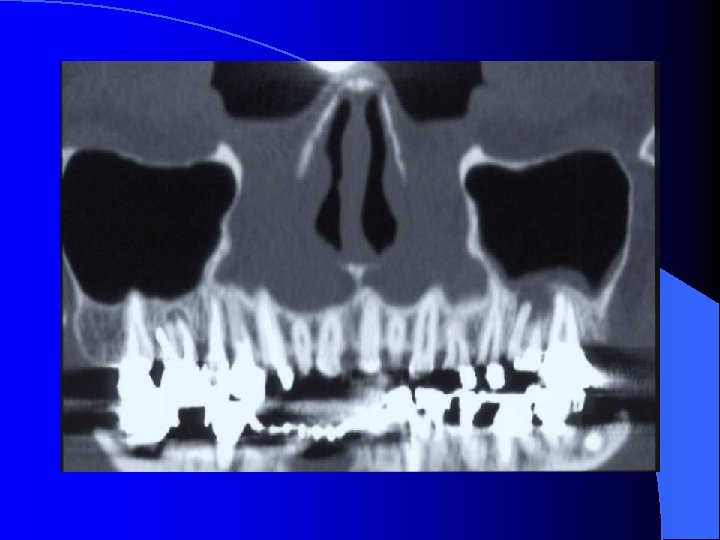

MALADIES INFECTIEUSES RHINO SINUSIENNES SINUSITE MAXILLAIRE CHRONIQUE IMAGERIE Radiographies standard Blondeau (nez-menton-plaque): CE, Niveaux hydro-aérique Panoramique dentaire: Etat bucco-dentaire, signes unilatéraux TDM crânio-faciale IRM crânio-faciale

MALADIES INFECTIEUSES RHINO SINUSIENNES SINUSITE MAXILLAIRE CHRONIQUE TRAITEMENT Prise en charge Médico-Chirurgicale • Lavage des fosses nasales • Vaso-constricteurs locaux • ATB probabiliste orale 21 jours • Méatotomie moyenne endonasale • Voie vestibulaire type Caldwell-Luc Objectif: • Levée de l’obstacle ostial • Prélèvements bactério et anapath (Dc différentiel) • Suppression du foyer infectieux (truffe aspergillaire, foyer dentaire)

MALADIES INFECTIEUSES RHINO SINUSIENNES SINUSITE MAXILLAIRE CHRONIQUE FORMES CLINIQUES SMC Aspergillaire: • ATCD de soins dentaires maxillaires • RX, TDM: Micro-opacité de tonalité métallique au sein d’une opacité complète du sinus maxillaire • Prise en charge chirurgicale : Méatotomie moyenne endonasale pour détersion du sinus maxillaire et exérèse de la truffe aspergillaire Voie vestibulaire type Caldwell-Luc • Aucune indication à un traitement médical antimycosique SMC de l’enfant: (rare) Contexte de pathologie générale à recher Mucoviscidose, Dysfonction ciliaire (Kartagener)